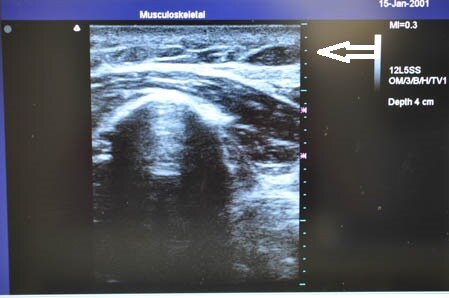

ではいつものように3Dタッチビュー(=超音波)で

皮下脂肪層を確認しながら見ていきましょう。

右ちからこぶ。 ↓ ↓ ↓

↓ ↓ ↓